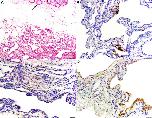

Idiopathic hypocalcemia in Thoroughbred (TB) foals causes tetany and seizures and is invariably fatal. Based upon the similarity of this disease with human familial hypoparathyroidism and occurrence only in the TB breed, we conducted a genetic investigation on two affected TB foals. Familial hypoparathyroidism was identified, and pedigree analysis suggested an autosomal recessive (AR) mode of inheritance. We performed whole-genome sequencing of the two foals, their unaffected dams and four unaffected, unrelated TB horses. Both homozygosity mapping and an association analysis were used to prioritize potential genetic variants. Of the 2,808 variants that significantly associated with the phenotype using an AR mode of inheritance (P<0.02) and located within a region of homozygosity, 1,507 (54%) were located in a 9.7 Mb region on chr4 (44.9-54.6 Mb). Within this region, a nonsense variant (RAPGEF5 c.2624C>A,p.Ser875*) was significantly associated with the hypoparathyroid phenotype (Pallelic = 0.008). Affected foals were homozygous for the variant, with two additional affected foals subsequently confirmed in 2019. Necropsies of all affected foals failed to identify any histologically normal parathyroid glands. Because the nonsense mutation in RAPGEF5 was near the C-terminal end of the protein, the impact on protein function was unclear. Therefore, we tested the variant in our Xenopus overexpression model and demonstrated RAPGEF5 loss-of-function. This RAPGEF5 variant represents the first genetic variant for hypoparathyroidism identified in any domestic animal species.